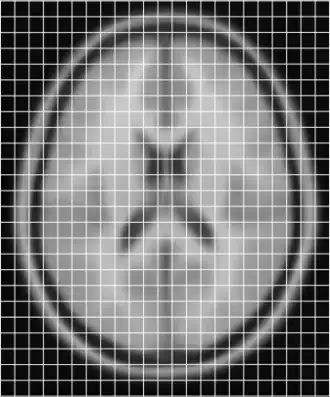

resampled using like

Note that the output file now has the same sampling as the original model.